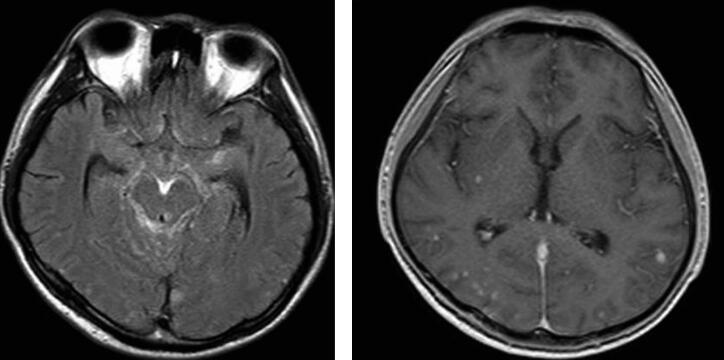

扫描采用PHILIPS ACHIEVA 1.5T超导型磁共振扫描系统,8通道头部线圈,患者取仰卧位,双上肢平置于身体两侧。采用T1加权成像(T1WI)和FLAIR,FFE序列,进行横断位及矢位扫描。采用钆布醇注射液7.5ml,经手背静脉注入,3分钟后扫描。MRI表现见图1。

图1脑内多发结核瘤伴结核性脑膜炎

脑内多发结核瘤伴结核性脑膜炎